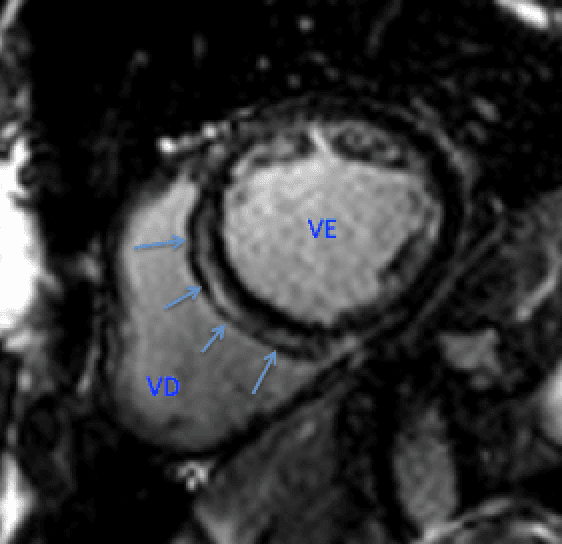

La Miocardiopatía Arritmogénica del Ventrículo Derecho (MAVD) es una enfermedad hereditaria que se caracteriza por el reemplazo progresivo de tejido fibro- grasoso, predominantemente en el ventrículo …